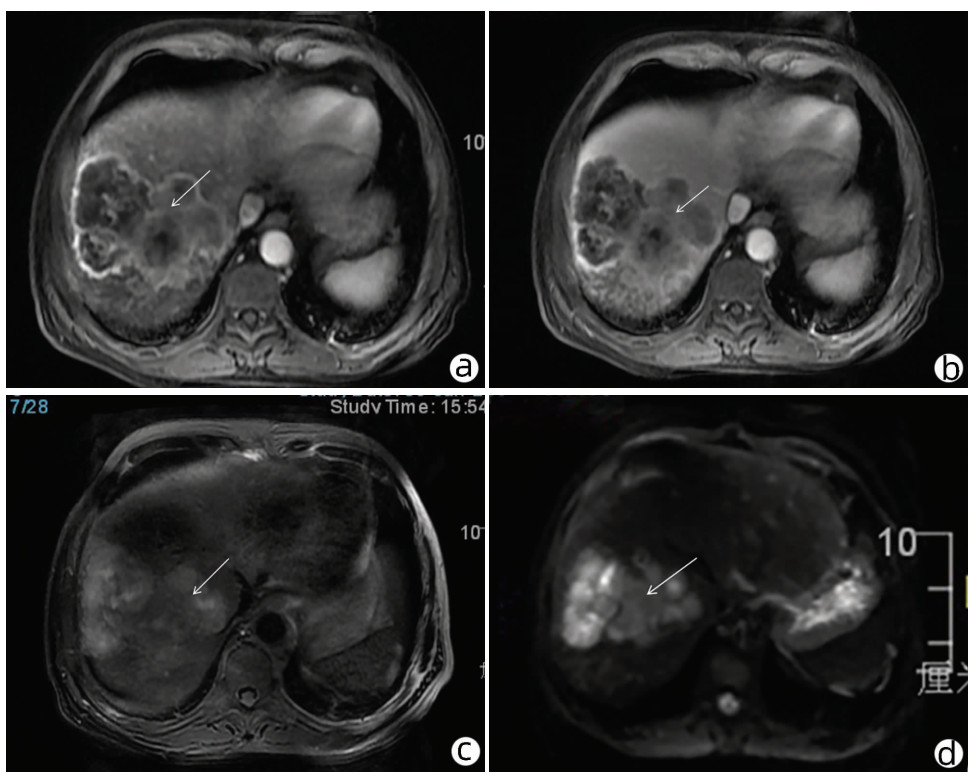

局部栓塞联合靶向免疫综合治疗肝肉瘤样癌1例报告

摘要(1328) HTML (453) PDF (3487KB)(83)

摘要: